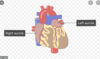

What do the tricuspid and mitral valves separate?

- tricuspid = right atrium and ventricle

- mitral = left atrium and ventricle

When looking at the heart anteriorly, out of the pulmonary veins supplying oxygenated blood from the lungs to the heart, and the pulmonary arteries carrying de-oxygenated blood from the heart to the lungs, which is superior and inferior?

- pulmonary arteries are superior

- pulmonary veins are inferior